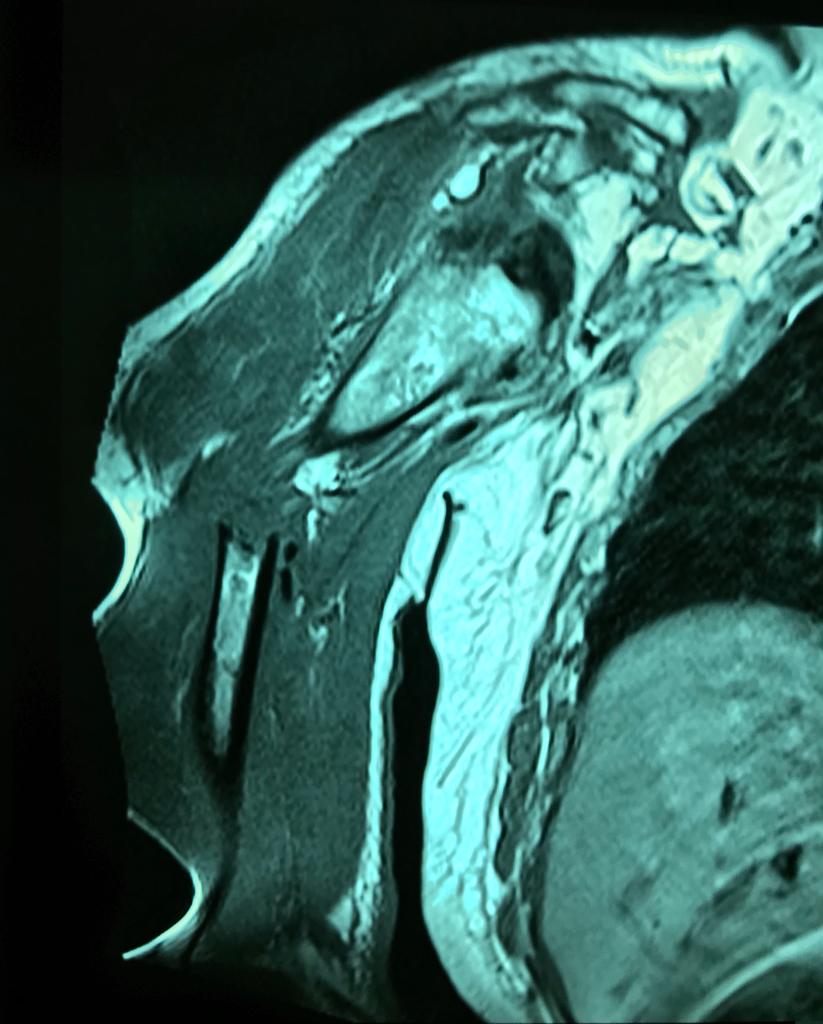

Pacientes con luzación glehumeral anterior y fractura diafisiaria del humero, de un mes de evolución. Se complica con una oclusión de un segmento de la arteria subclavia-axilar, secundaria a trombosis.

Las lesiones de vasculares asociadas a fracturas y luxaciones del hombro son poco frecuentes, aunque potencialmente muy graves por lo que requieren un diagnóstico y actuación urgentes. Debido a la proximidad anatómica, pueden coexistir signos de compromiso de nervios mediano, radial y cubital.